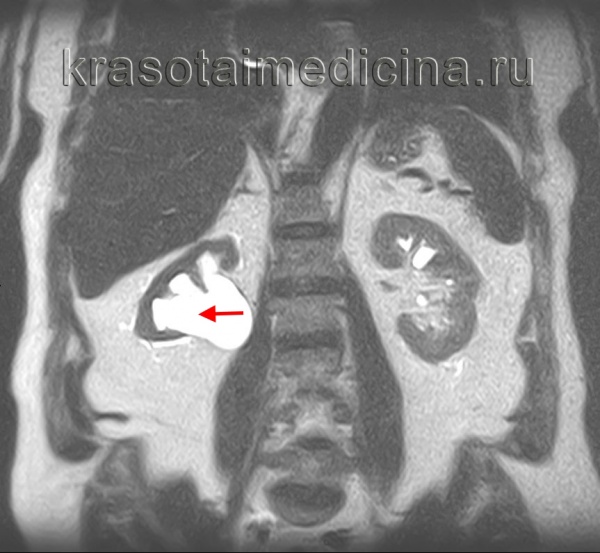

МРТ ОБП и забрюшинного пространства. Выраженное расширение чашечек и лоханки правой почки на фоне истончения ее паренхимы